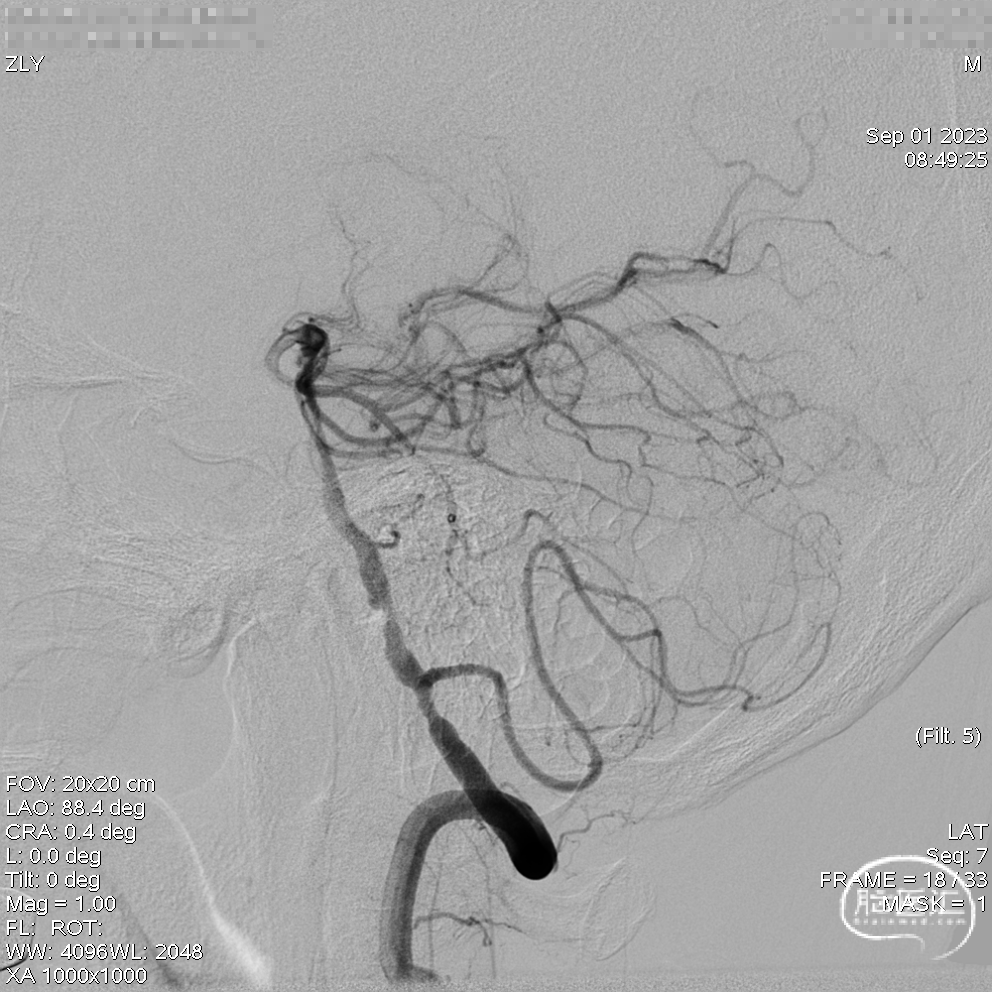

DSA示双侧椎动脉V4段狭窄,右侧为著且合并梭形动脉瘤。

术前DSA。